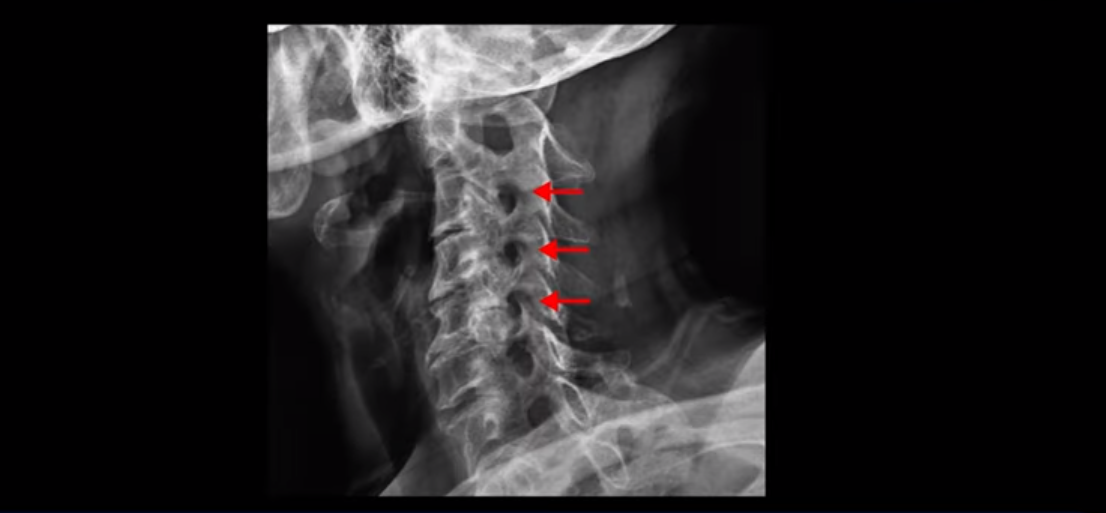

이 환자분 X-ray, MRI 보고 간단히 설명 드린 후 왜 목디스크 치료가 허리디스크에 비해 훨씬 더 쉬운지 자세히 설명 드리겠습니다.

X-ray 보시다시피 완전 일자목 거북목에다 여러 마디가 전부 다 퇴행이 심하며

뼈 모양의 변형도 매우 심합니다.

X-ray로 봐도 신경 구멍들이 좁아진 게 보입니다.

이런 걸 협착이라고 부르는 거죠. 이 분의 가장 불편한 증상은 20년간 아픈 만성적인 목통증과 어깨통증, 두통과 눈 통증인데 최근 들어 가증 불편한 증상은 목이 아예 돌아가지 않는 겁니다. 그래서 운전할 때도 사이드 미러를 보려면 몸을 돌리셨다고 하는데요. 주사 효과도 전혀 없고 대학병원에서도 디스크와 협착인데 그냥 약먹고 운동만 하라고 하면 이 환자는 어떻게 해야 할까요?

이 환자분도 아까 X-ray에서 보여드렸듯이 아주 심한 일자목, 거북목이 있고 그 결과로 목의 거의 모든 마디가 다 퇴행이 진행되어 있죠. 즉 거북목은 모든 목질환, 특히 목디스크, 목협착증의 어머니 질환이며 그래서 목디스크를 치료하기 위해서는 반드시 거북목 때문에 짧아지고 뭉치고 굳고 뒤틀린 목 주변 근육들을 잘 치료해줘야 합니다.